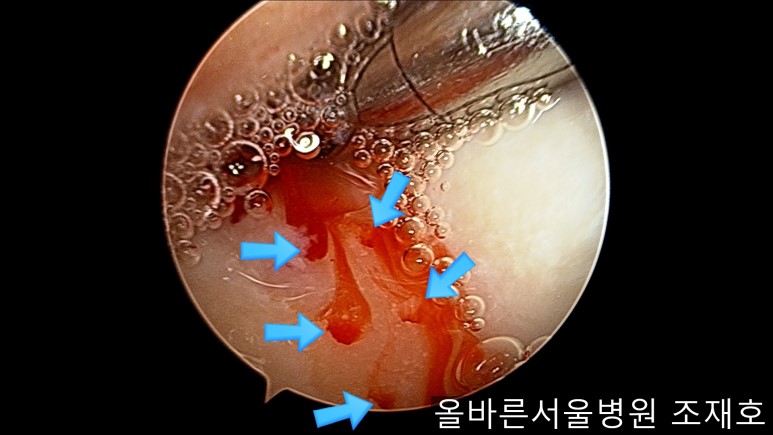

通过关节镜图像可看到:由于内侧股骨髁软骨损伤骨头已经显露出来。

image_9824311181519375935940.jpg

胫骨上端的软骨损伤严重,也露出了骨头。

image_9926851221519375935929.jpg

正是缺失软骨的部位碰到一起,引发剧烈疼痛,腿部逐渐变形。